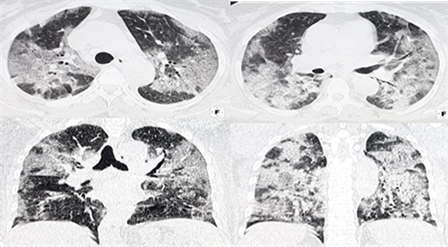

Mixed appearance of lesions was the most common with 45.5% (n = 92). Lung lesions were more frequent in the periphery with 57.4% (n = 116). They were bilateral in the majority of patients with 98% (n = 198).This is shown in Table 2 and Figure 1 and Figure 2.

Figure 1. Axial CT scan images with parenchymal window showing areas of frosted glass and condensation.

Figure 2. Axial CT scan images and coronal reconstructions withparenchymal window showing areas in frosted glass with “crazy paving”.

Mixed appearance of lesions was the most common with 45.5% (n = 92). Lung lesions were more frequent in the periphery with 57.4% (n = 116). They were bilateral in the majority of patients with 98% (n = 198). A wide variety of lung lesions have been described for COVID-19 on chest CT. The most common CT manifestations and their characteristics include frosted glass opacities (87%), bilateral lesion involvement (80%), peripheral distribution (75%), multilobar involvement (89%), posterior topography of the lesions (80%) and parenchymal condensations (33%) [3]. The most characteristic CT abnormalities of COVID-19 pneumonia are areas of ground glass (approximately 80% of cases), multifocal, bilateral, asymmetric. The involvement classically predominates in the peripheral, posterior and basal regions [15]. Yu et al. claimed that with regard to the different types of pulmonary opacities, most patients showed mixed lesions (ground glass and union) in both study groups (27 of 50, 54%) and group 2 (11 of 20, 55%) [16]. Bernheim et al. report a predominance of round lesions, i.e. 54% in a series of 121 [5]. According to these same authors, the peripheral distribution predominated with 52% [9]. Most of the patients had bilateral pulmonary involvement, both central and peripherally distributed. The pure central distribution of lesions and unilateral pulmonary localization was rare [16].